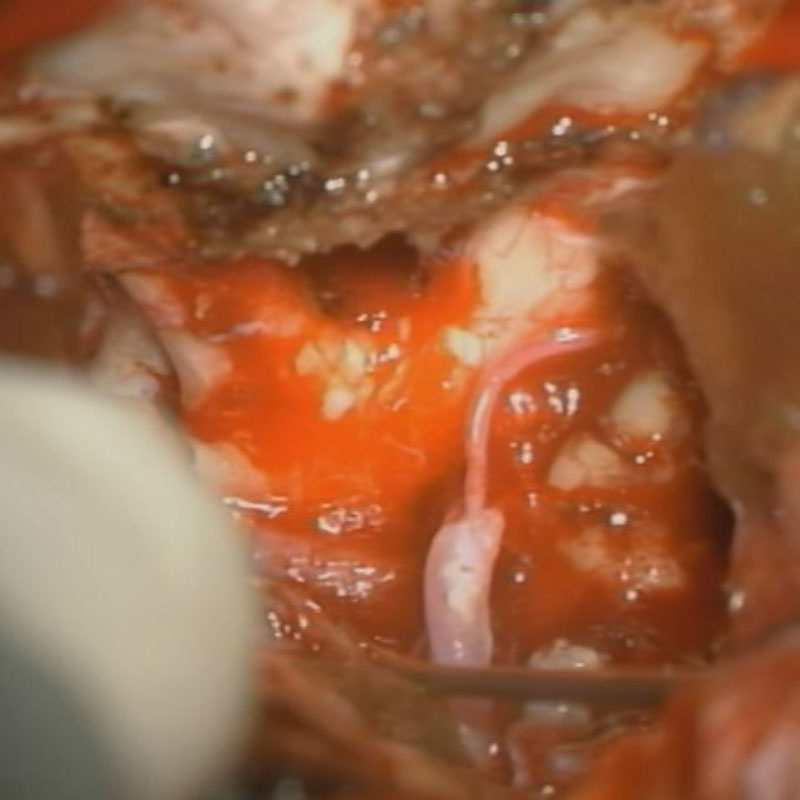

No.’22_117 摘出 前

No.’22_117  摘出 中